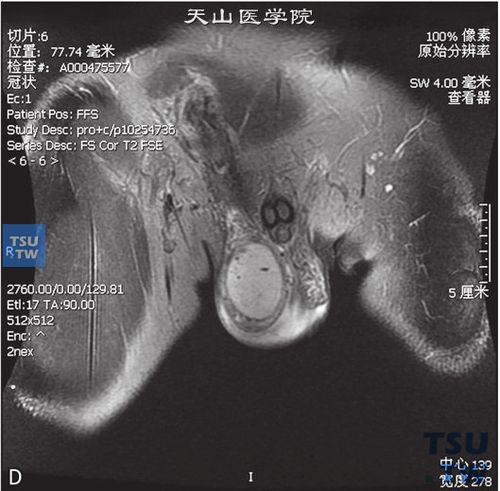

睾丸女性化综合征图

睾丸女性化综合征图,睾丸退化综合征女性